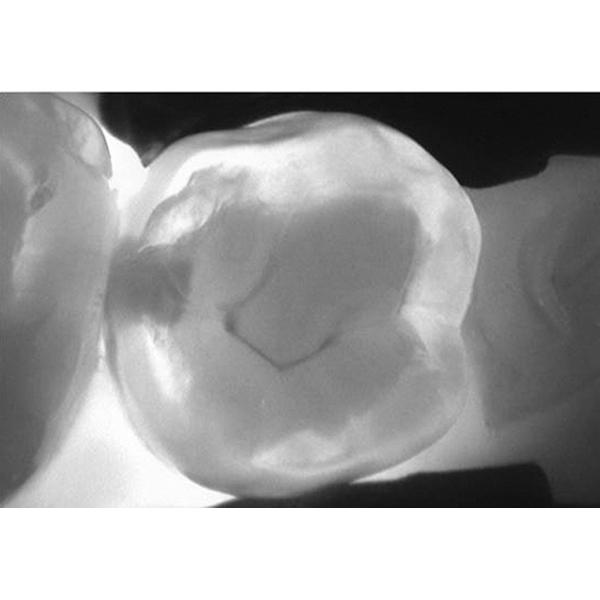

The new KaVo DIAGNOcam is the first camera system that uses the tooth’s structure to verify caries diagnosis. To do this, the tooth is transilluminated utilising light of a specific wavelength and used like a light conductor. A digital video camera records the image and displays it live on a computer screen. Carious lesions are displayed as dark shadows. With its DIFOTI technology (Digital Imaging Fiberoptic Transillumination), DIAGNOcam offers high diagnostic safety which is comparable or superior to X-ray diagnosis in many cases, in particular with regard to approximal and occlusal caries. Furthermore, it is possible to show certain kinds of secondary caries and cracks. The X-ray free device thereby allows early and very gentle caries detection. Compared to other methods, the clinical significance is not distorted through plaque deposits.